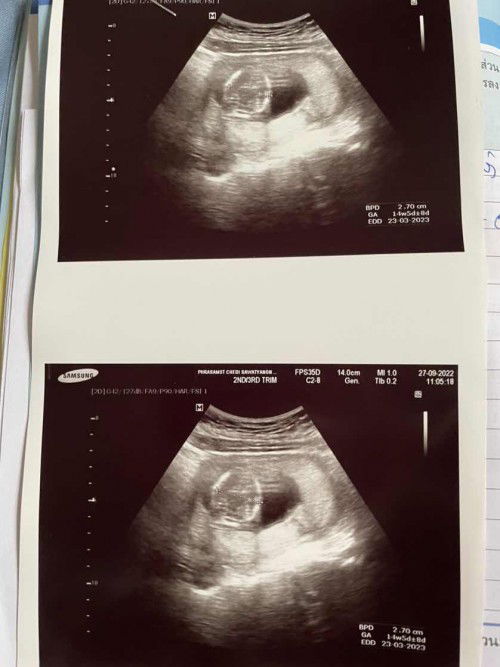

ตอนตั้งครรภ์แรกๆเราค่อนข้างเครียดกับการเลือกโรงพยาบาลฝากครรภ์มากค่ะ เพราะเดิมตัวเองเป็นซึมเศร้าและโรควิตกกังวลอยู่แล้ว(แต่พอรู้ว่ามีลูกก็ดีขึ้นมากๆเลยค่ะ) กังวลไปหมด กลัวเขาจะตรวจลูกในท้องเราไม่ดี ก็ศึกษาหลายๆที่ทั้งเสียตังฝากพิเศษและไม่เสียตัง ปกติแล้วไม่เคยใช้บริการโรงพยาบาลรัฐเลยค่ะ เข้าโรงพยาบาลเอกชนตามประกันสังคมตลอด แล้วก็กลัวโรงพยาบาลรัฐไปเอง55555 จนมีเพื่อนที่พึ่งคลอดแนะนำให้ไปฝากครรภ์ที่โรงพยาบาลรัฐ ตอนแรกคือไม่เอาเลยค่ะ กลัวตั้งแต่ยังไม่ลองไป จนเพื่อนกล่อมว่ามันดีนะ ไม่เสียค่าใช้จ่าย เก็บตั้งไว้ตอนคลอดดีกว่า ให้ลองไปดูครั้งแรกถ้าไม่โอเคค่อยย้ายไปฝากที่อื่น เราก็เลยลองไปดู พอไปถึงบอกเลยว่าประทับใจ ป้าหมอคนนึงใจดีมากค่ะ(แต่คนอื่นๆก็จะเสียงแข็งหน่อยแต่พอรับได้ค่ะไม่ร้ายแรง)ให้คำแนะนำดีมาก พอป้าหมอรู้ว่าเราเป็นซึมเศร้าและวิตกกังวลอยู่แล้ว ป้าหมอจะคอยถามทุกครั้งที่ไปตรวจว่า เป็นยังไงบ้าง ดีขึ้นมั้ย ไม่เศร้านะ เข้มแข็งนะคุณแม่ ลูกจะได้แข็งแรง ป้าหมอให้คำปรึกษาได้ดีมากๆเลยค่ะ แถมมีตรวจคัดกรองดาวน์ซิมโดรมฟรีด้วย ป้าหมอจะถามตั้งแต่ครั้งแรกที่ไปฝากเลยค่ะว่าสนใจจะตรวจคัดกรองดาวน์ซินโดรมมั้ย แม่ก็ตรวจทุกอย่างที่ป้าหมอแนะนำมา และทุกครั้งที่ไปหาหมอไม่เสียค่าใช้จ่ายสักบาทจริงๆค่ะ คนไทยทุกคนทุกสิทธิ์ฝากครรภ์ฟรีหมด เลยอยากจะมาแนะนำแม่ๆท่านอื่นที่อาจจะมีความคิดแบบเราให้ลองไปใช้สิทธิ์กันดูนะคะ โรงพยาบาลรัฐ(บางโรงพยาบาล)ไม่ได้น่ากลัวอย่างที่คิดค่ะ ตอนนี้อีแม่สบายใจมากๆเลยค่ะ คิดไม่ผิดที่เลือกไปฝากกับโรงพยาบาลนี้🥰 ตอนนี้ 15w4d แล้วค่ะ พึ่งไปซาวด์คัดกรองดาวน์กับเจาะเลือดคัดกรองดาวน์มาค่ะ ผลซาวด์ปกติดี แต่รอผลเลือดประมาณ10วันค่ะ #ท้องแรกคะ